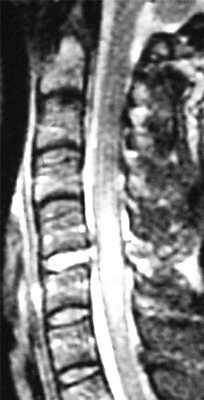

МРТ шейного отдела позвоночника. Т2-взвешенная сагитальная МРТ. Острая травма с повреждением задних элементов позвонков и отеком спинного мозга.